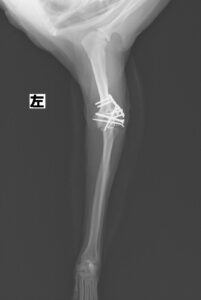

階段からころげおちてかかりつけ医を受診し、X線にて左側「上腕骨外顆骨折」を認めたため、当院の整形外科にご紹介いただきました。この症例は、尺骨の骨切り術を併用し外顆の骨折部分を整復しています。術後の経過は良好で、手術から7ヶ月後に尺骨のインプラントを除去し、治療終了としました。